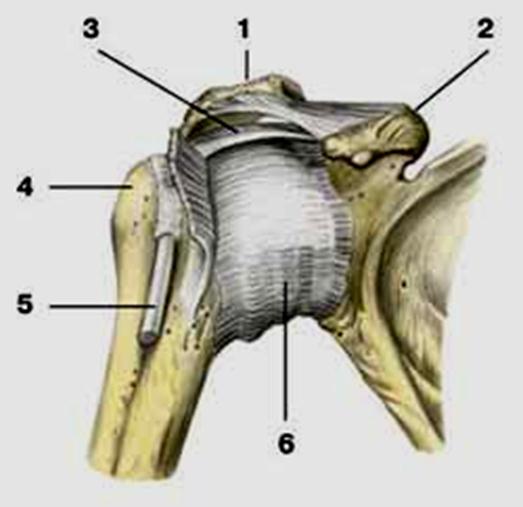

S: Стрелка указывает на art. ### (латинский язык).

S: Стрелка указывает на lig....

Стрелка указывает на lig....

Стрелка указывает на lig....

S: Стрелка указывает на...

S: Стрелка указывает на lig....

S: Цифрой 6 обозначена ### плечевого сустава (русский язык).